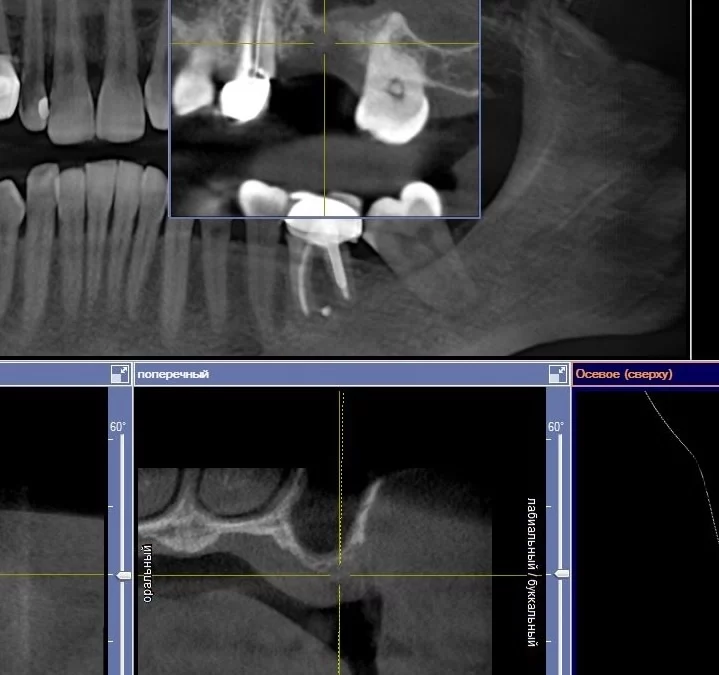

Юрий Гузеев | Клинический кейс YG-133

Реферативный пациент, удаление несостоятельных имплантов. Горизонтальная атрофия фронтальный отдел. - НКР ауто + ксено. - Создание барьера - титановая пластина. - Открытие через 6 месяцев. - Импланты MIS C1....